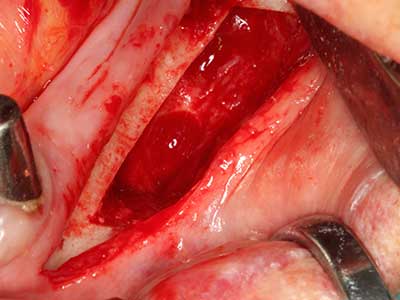

Indication: Preparation near nerves

As noted above, indications for piezo surgery can also be found in the field of conservative dental surgery. Special working tips simplify the exposure of root tips and make it easier to protect nerves and sinus mucous membranes, particularly in the lower premolar and upper posterior tooth regions. Angled diamond tips are used to precisely prepare the resection cavity for the retrograde root filler material for unsealed apical obturation. The ultrasonic technology means the tips can be very slender, which improves the view and the size of the access cavity. As a result, the application of ultrasonic surgery for this indication is one of the standard procedures for apical resection (Del Fabbro, Tsesis et al. 2010, Scarano, Artese et al. 2012).

Indication: Apical resection

When surgical procedures are performed on bone in the immediate vicinity of sensitive structures such as blood vessels or nerves, rotary instruments pose a significant risk of iatrogenic injury. Piezoelectric devices can be helpful for preparation of bone covers and removal of hard tissue close to nerves, particularly for exposure of nerves after iatrogenic injury but also during nerve lateralization for resective and reconstructive procedures or implant placement (Fig. 17-20). Light contact between the piezotip and the nerve does not generally result in damage but proceeding incautiously with saw-like motions or attachments where a residual bone substrate remains may cause temporary or even permanent nerve damage. However, the risk of damage is considered to be substantially lower than when using saws or milling instruments (Pereira, Gealh et al. 2014).